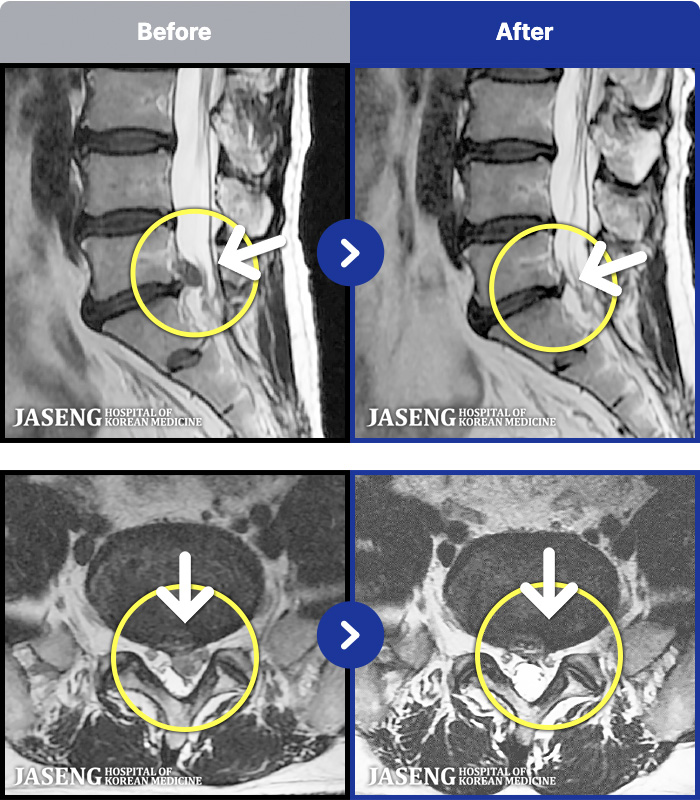

1,293 MRI ũ ʸ Ȯϼ.